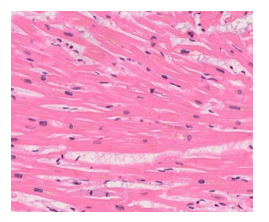

myocardial infract (early stages)

normal heart muscle

1- ischemic necrosis

Myocardial infract early stages